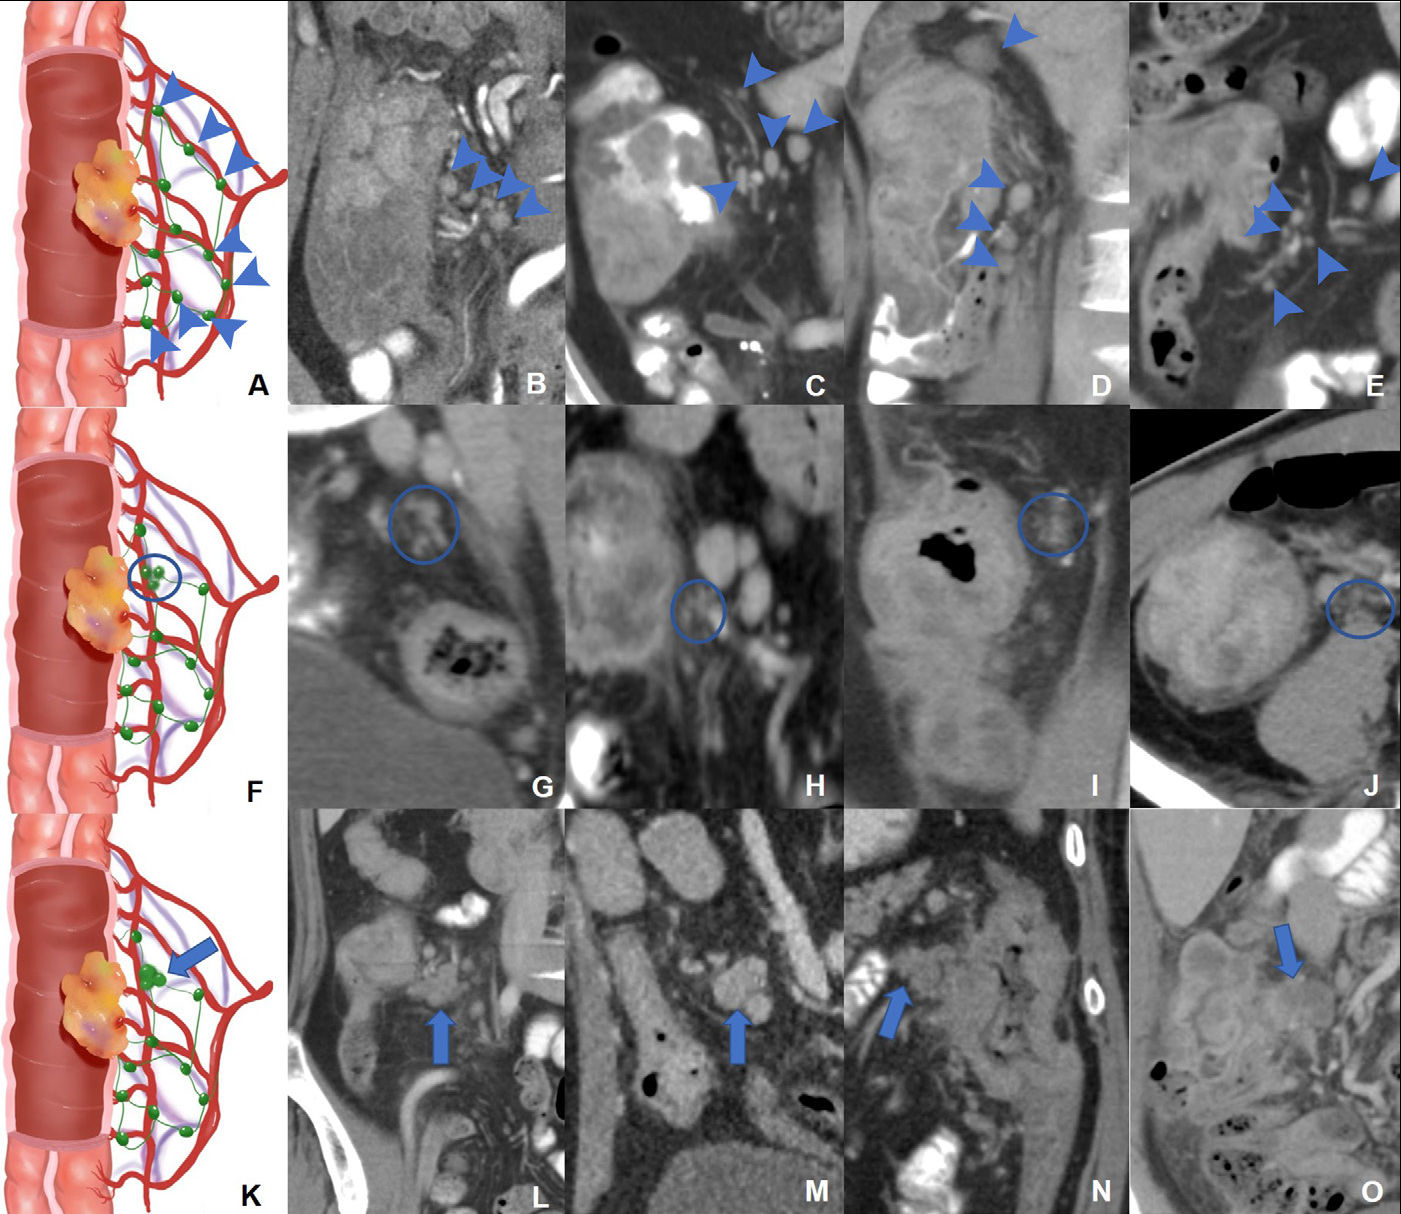

Meanwhile, researchers from China have developed a novel method to improve lymph node staging in colon cancer, offering potential benefits for tailored treatment and better patient outcomes.